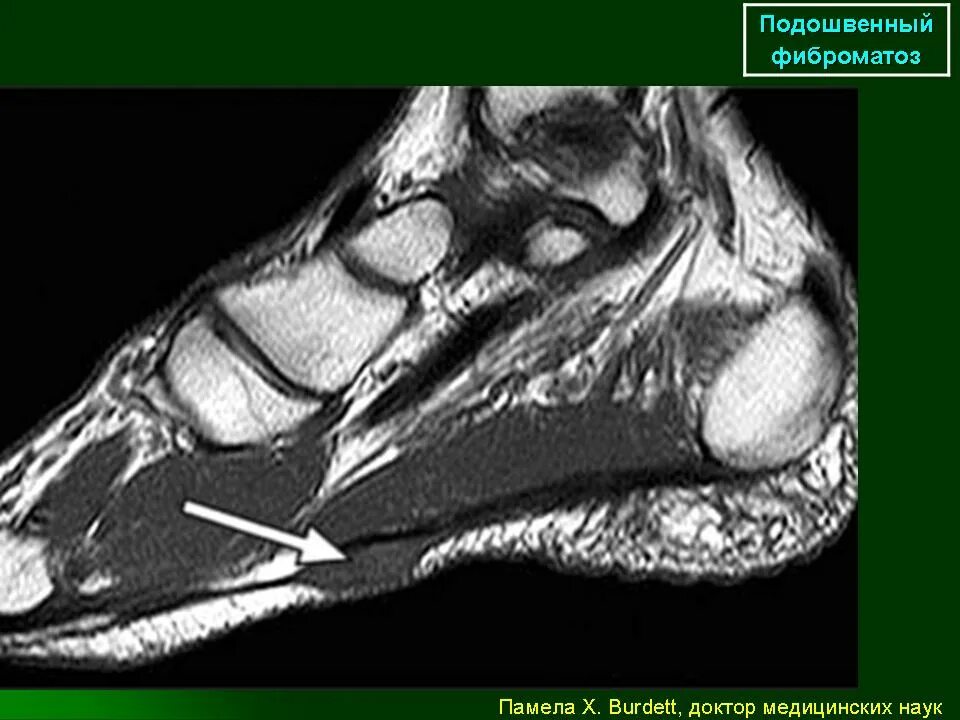

Фиброматоз мягких